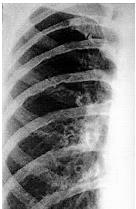

Homem de 25 anos apresenta pressão arterial (PA) variando de 160 × 110 a 170 × 120 mmHg. Chama atenção na sua radiografia de tórax entalhamentos em alguns arcos costais (figura abaixo).

medir a PA em membros inferiores e realizar tomografia de aorta.